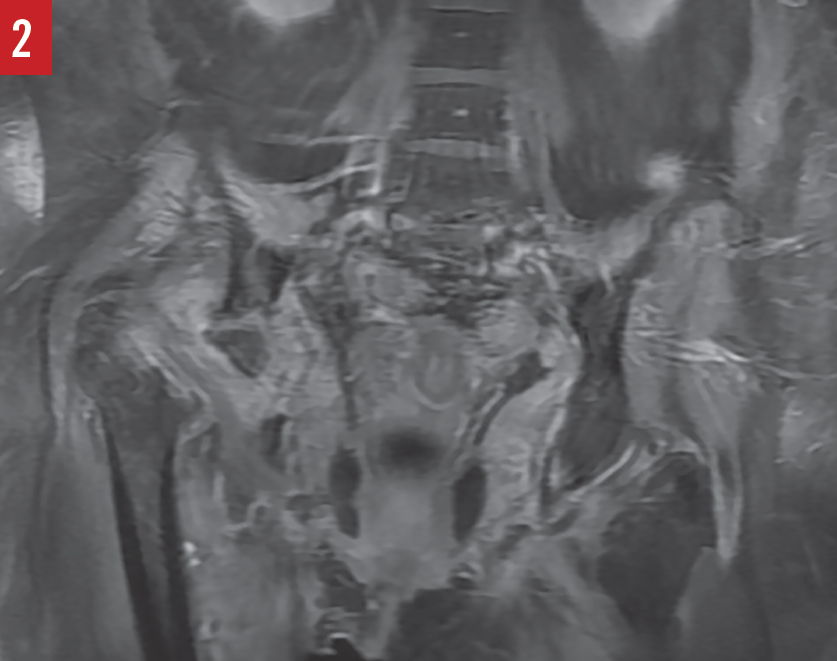

from radiologyassistant.nl

The Radiology Assistant Hip pathology in Children

The Radiology Assistant Hip pathology in Children Osteomyelitis Symptoms Hip Treatment is with antibiotics and sometimes surgery. The following are the most common symptoms of osteomyelitis; Bacteria can enter your system at a surgical site, such as the site of a hip replacement or bone fracture repair. Fever (may be high when osteomyelitis occurs as the result of a blood infection) pain and tenderness in the affected area. Suspect acute. Osteomyelitis Symptoms Hip.